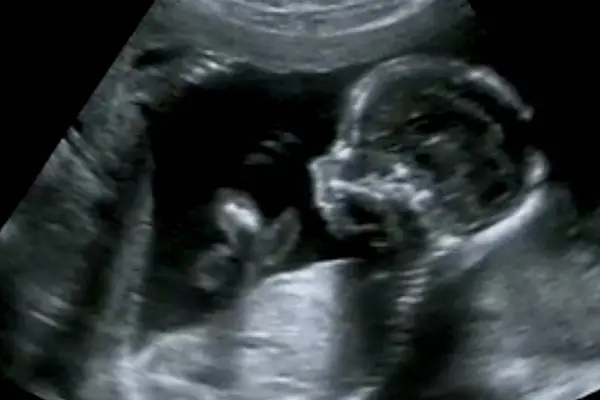

Ultraschall ist mehr als nur Babyfernsehen. Wir gehen der Sache auf den Grund.

3D-/4D-Ultraschall bietet werdenden Eltern detaillierte und bewegte Bilder ihres Ungeborenen, um Entwicklungen besser zu verstehen.